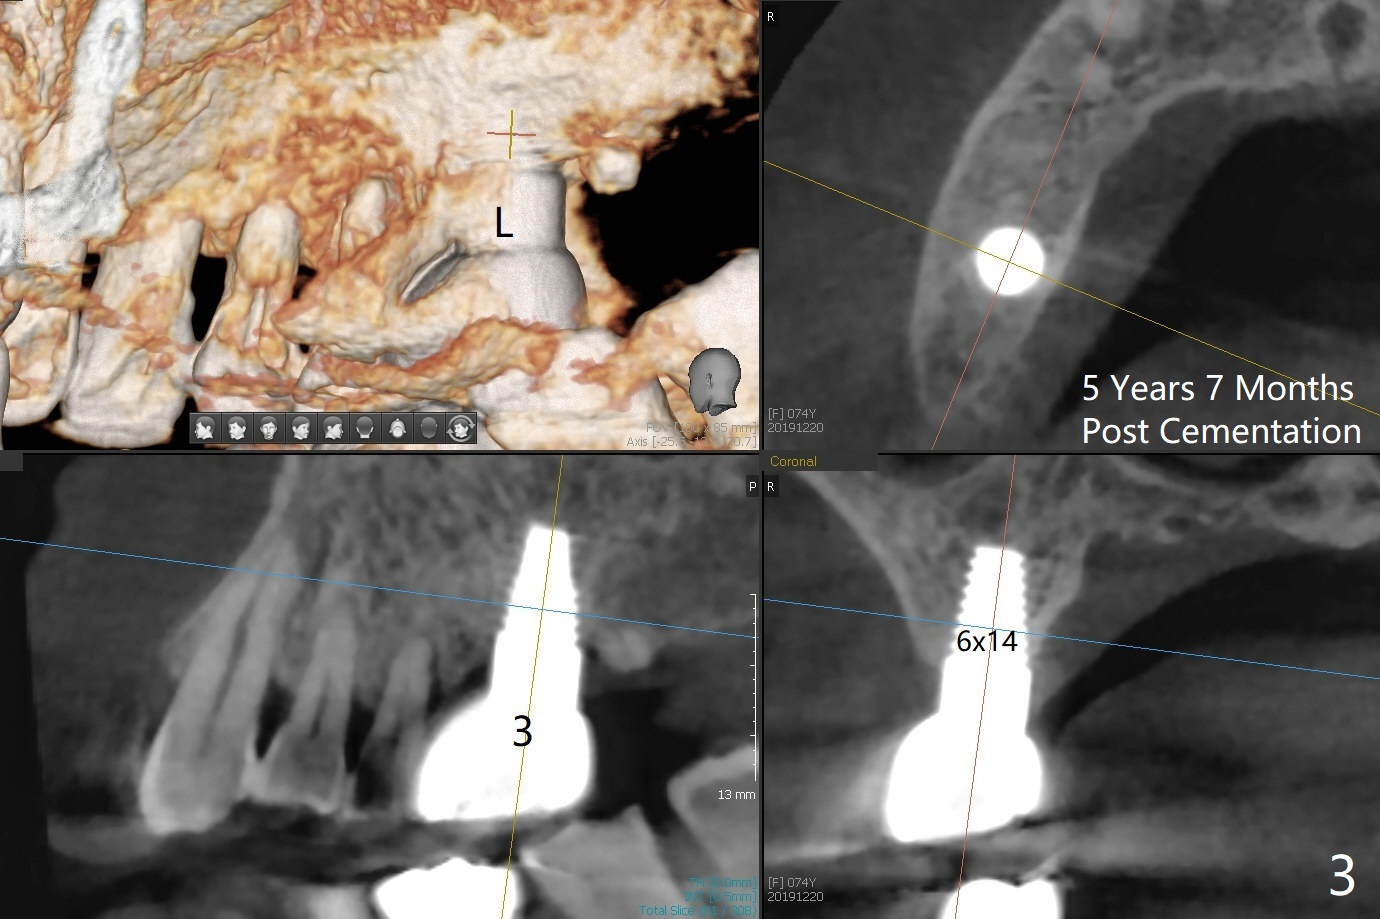

A 74-year-old woman returns for #19 implant consul-tation 5 years 7 months post cementa-tion at #3 (Fig.1). Since the implant at #3 (6x14 mm) has less ideal trajectory associated with free hand placement (Fig.3 (mild distolingual (L) thread exposure; Fig.1,4 (distal placemennt), guide will be fabricated for #19 implant placement. The lingual plate is thick and dense (Fig.2 L). To prevent drill and implant deviation buccally, a 5x11.5 mm implant will be placed as lingual as possible. A 5 mm cortical drill will be used before 2.2-4.5 mm ones being used for depth. The 4.0 mm drill will reach the final depth (apical underprep). A 17 mm long tissue-level implant will be placed. 17-5.5=11.5 mm (thread portion); 1.2 mm drill tip for the rough surface. Prepare 3.5x14 or 17 mm dummy implant to test the depth.